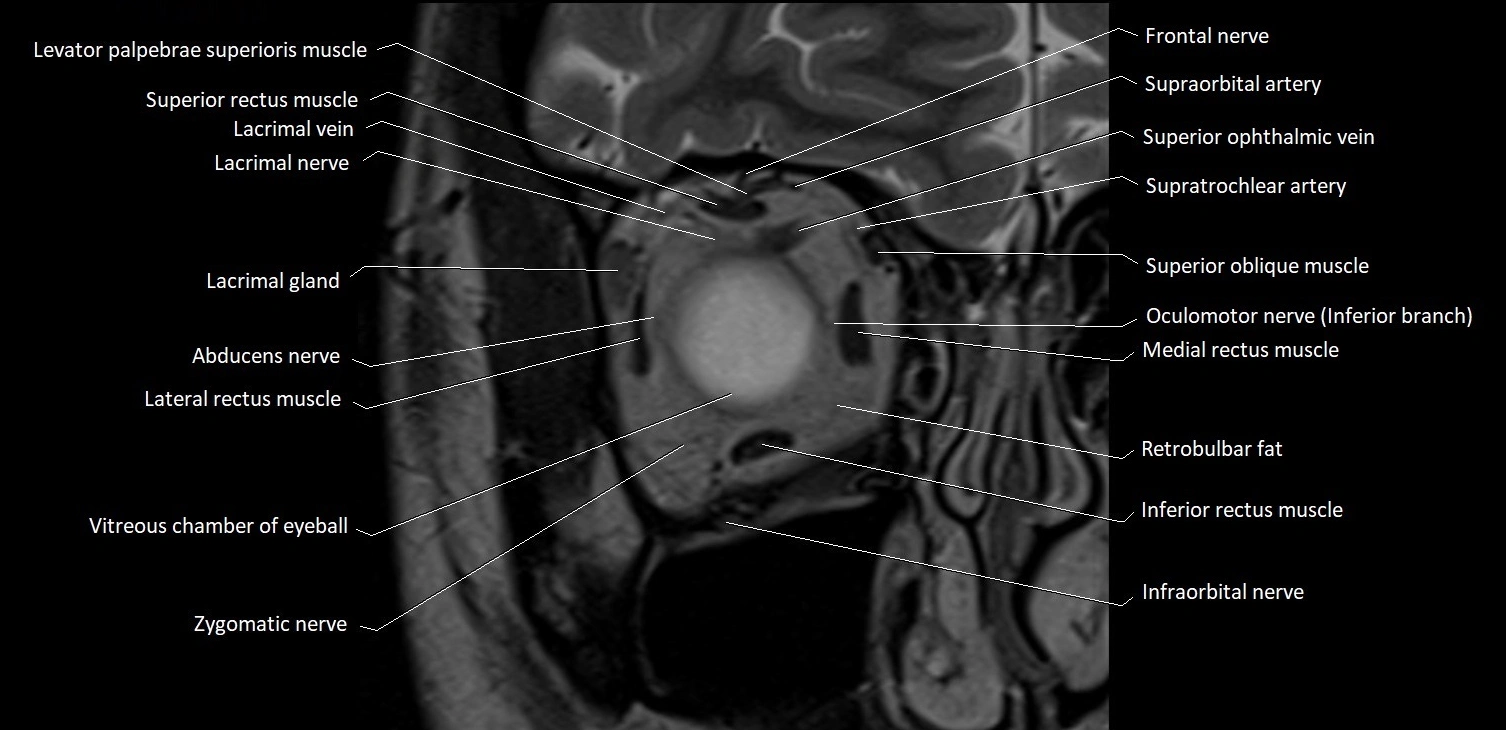

MRI images